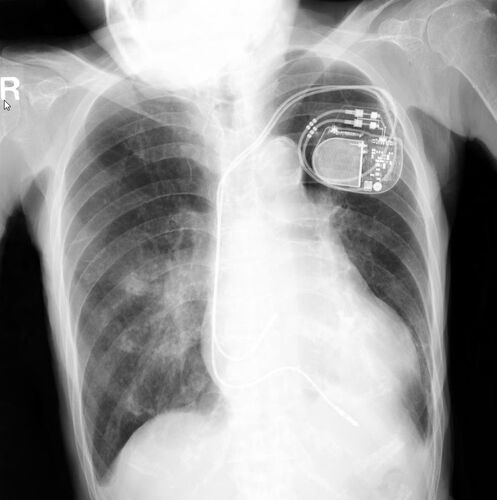

80才代女性。CRBBB+LAD+(I度房室ブロック)でその後CAVBとなり、DDD-PMを植え込まれた方です。ECG-207の症例の2年後です。 胸部レントゲンで、心房・心室に各々リードが入っているのが、わかります。皮下脂肪が無いことより、栄養状態の悪化が理解できます。…